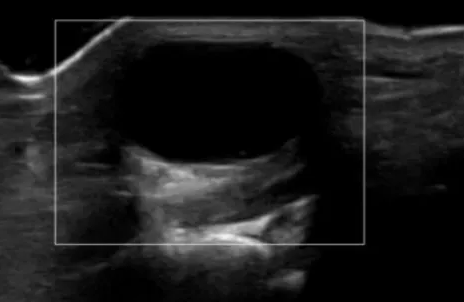

可视化针刀微创治疗:是一种在超声实时、动态引导下,利用特制“小针刀”进行操作,实现囊肿灭活与吸收的微创技术。